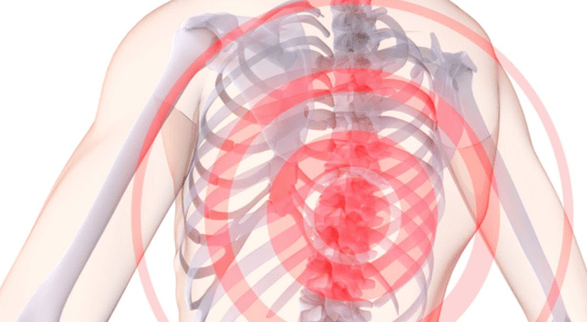

胸部骨软骨病有哪些症状?首先是疼痛,包括:

- 肩胛间和肋间神经痛腰痛;

- 左侧胸部疼痛;

- 手部疼痛,当举起并到达指尖时疼痛加剧;

- 弯曲时疼痛;

乳房骨软骨病引起的疼痛可以通过不同的方式表现出来。有时这些是轻微的刺痛或钝痛,出现在下午晚些时候,并在进行体力活动(例如散步)后消失。这通常是胸椎骨软骨病的初始阶段的进展情况,此时椎间盘尚未受到严重影响。

在疾病发展的后期,疼痛症状通常表现为腰痛。疼痛明显、剧烈,干扰正常呼吸,不必要的动作只会加剧情况。腰痛通常是在长时间不活动后开始的,例如在计算机上静态工作几个小时后。

什么被认为是疾病的恶化?这个术语指的是剧烈的疼痛。如果患者感到明显不适,出现熟悉的腰痛和胸部钝痛,并放射至腹膜、腰部和手臂,那么就该高度关注该疾病了。